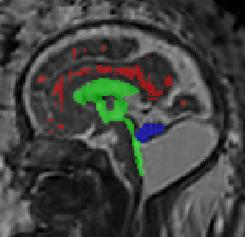

Limiting failures of machine learning systems is of paramount importance for safety-critical applications. In order to improve the robustness of machine learning systems, Distributionally Robust Optimization (DRO) has been proposed as a generalization of Empirical Risk Minimization (ERM). However, its use in deep learning has been severely restricted due to the relative inefficiency of the optimizers available for DRO in comparison to the wide-spread variants of Stochastic Gradient Descent (SGD) optimizers for ERM. We propose SGD with hardness weighted sampling, a principled and efficient optimization method for DRO in machine learning that is particularly suited in the context of deep learning. Similar to a hard example mining strategy in practice, the proposed algorithm is straightforward to implement and computationally as efficient as SGD-based optimizers used for deep learning, requiring minimal overhead computation. In contrast to typical ad hoc hard mining approaches, we prove the convergence of our DRO algorithm for over-parameterized deep learning networks with ReLU activation and a finite number of layers and parameters. Our experiments on fetal brain 3D MRI segmentation and brain tumor segmentation in MRI demonstrate the feasibility and the usefulness of our approach. Using our hardness weighted sampling for training a state-of-the-art deep learning pipeline leads to improved robustness to anatomical variabilities in automatic fetal brain 3D MRI segmentation using deep learning and to improved robustness to the image protocol variations in brain tumor segmentation. Our code is available at https://github.com/LucasFidon/HardnessWeightedSampler.